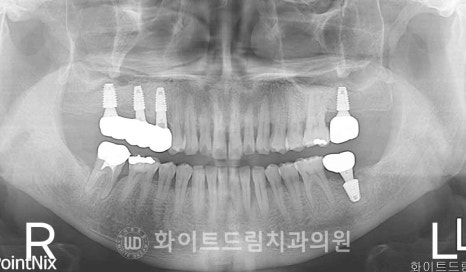

환자분의 초진 x-ray 사진부터 보겠습니다.

양측 어금니 부위의 치아들은

뿌리 주변으로 치주염과 골흡수가 상당히 진행된 모습을 보이고 있었습니다.

치근을 잡아주는 잇몸뼈가 많이 녹아 있어 지지력이 거의 없었고,

왼쪽 상악 어금니 치아는 하악 어금니 치아의 상실로

치아가 하방으로 내려오는 정출까지 나타나면서

더 이상 보존이 어려운 상태였죠.

환자분의 경우 오른쪽 상·하악 어금니는 임플란트가 바로 식립 가능한 상태였지만,

왼쪽 상악 어금니 부위는 골흡수가 더 심해 즉시 식립이 어려운 상태였기 때문입니다.